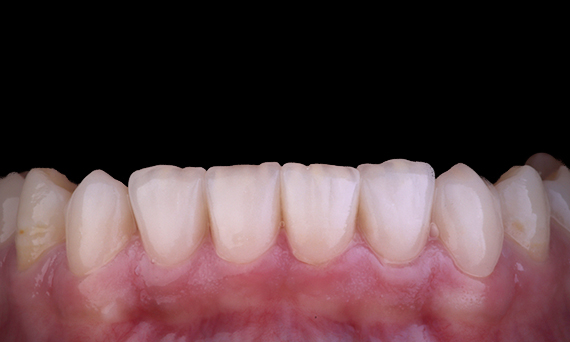

Often patients are unaware of the cracks or cavities in their teeth. It is only when a tooth hurts, or breaks do most patients realise the need to get their teeth checked. Often, we can pre-empt things like teeth cracking, based on the presence of existing cracks, heavy occlusion or history of previous tooth loss due to a crack. In this case, the patient had an asymptomatic cracked upper premolar tooth which was picked up during a routine dental check up. The patient was shown the photograph of the tooth and made aware of the situation, with a recommendation to having the tooth restored. However, the patient declined any treatment as he was not experiencing any symptoms from the tooth. 6 months later, the tooth cracked and now the patient could not put off treatment any further. The tooth was restored using CEREC with a ceramic-resin hybrid crown/onlay in one visit.

Dr Sahil Soni, Queensland, Australia